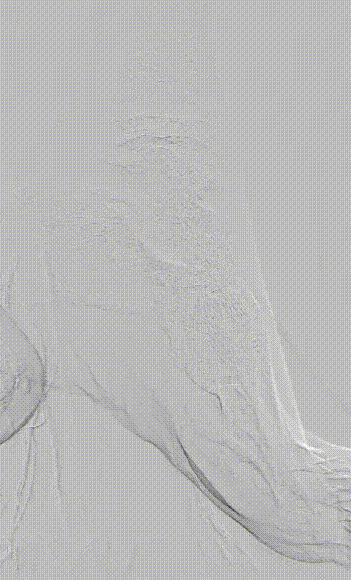

图为:术中造影评估 膝下踝下段